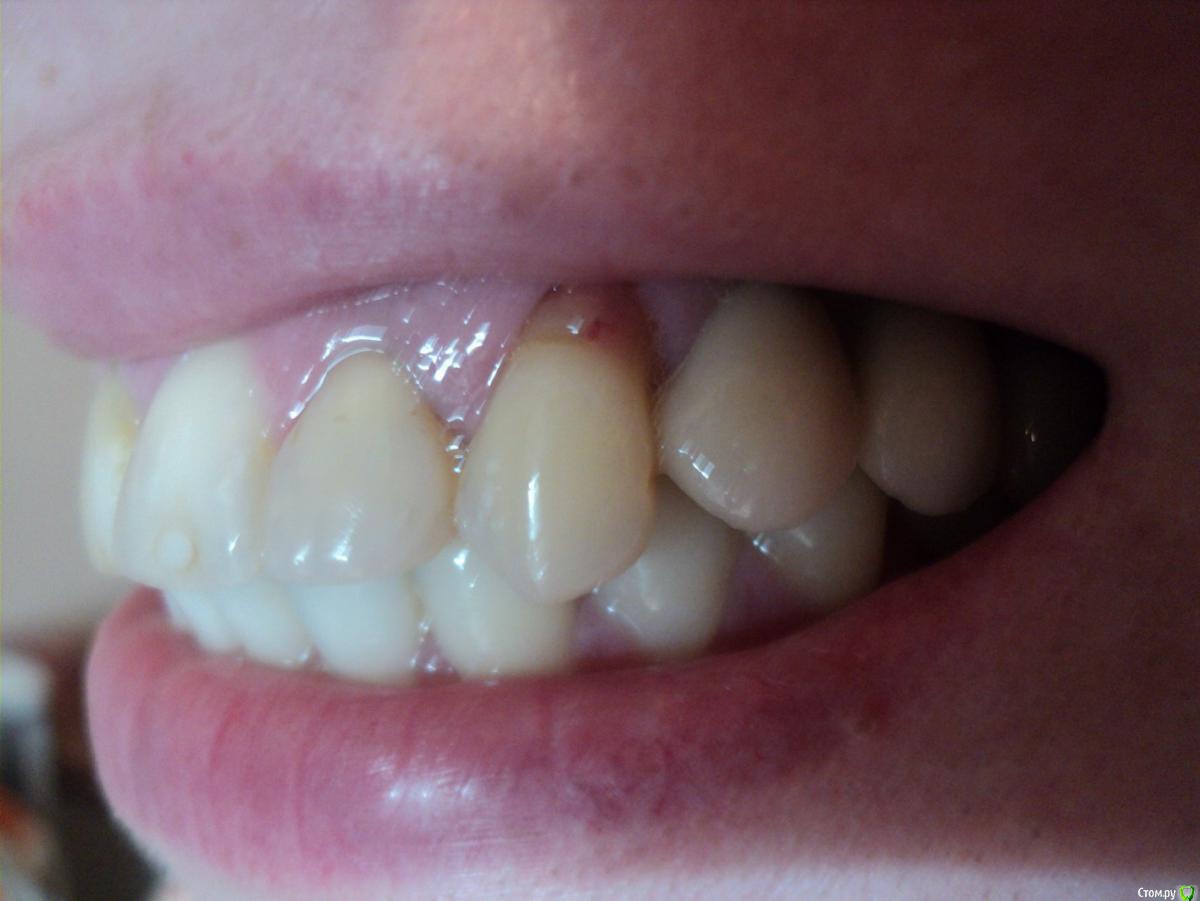

Arzella Опубликовано 2 мая, 2015 Поделиться Опубликовано 2 мая, 2015 Здравствуйте! После установки формирователя десны у соседнего зуба оголилась шейка. Подскажите, пожалуйста, что можно сделать в данном случае. Имплантолог считает, что ничего сделать нельзя, и вообще это не очень заметно и не страшно. А я боюсь теперь за этот зуб. Всем ответившим спасибо! Ссылка на комментарий

Arzella Опубликовано 2 мая, 2015 Автор Поделиться Опубликовано 2 мая, 2015 Не нравится, что коронки стоят выше уровня своих зубов. Еще напрягает, что имплант как-то уж совсем близко к клыку стоит. Ссылка на комментарий